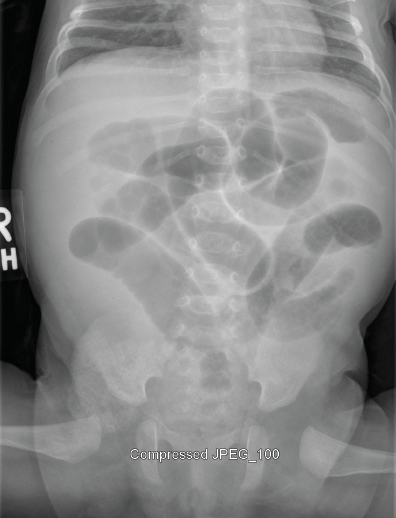

Kristen Samaddar, MD; Vanessa Celleri, MD

A 10-week-old girl presented to the emergency department after having had several episodes of nonbloody, nonbilious emesis and irritability.